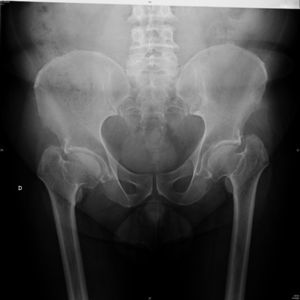

Caso clínicoVarón de 59 años con antecedente personal de diabetes mellitus tipo 2 en tratamiento con antidiabéticos orales, que acude a consulta de Reumatología por dolor inguinal bilateral y dorsolumbalgia de intensidad dolorosa progresiva, ambos de ritmo mecánico, que el paciente califica de muy intenso y que desencadenan dificultad progresiva para la deambulación; y por episodios de disnea de moderados esfuerzos, cuyo origen, estudiado por Neumología, era debido a dificultades en la expansión torácica. El cuadro doloroso no había presentado una respuesta satisfactoria a antiinflamatorios no esteroideos ni a opiáceos menores. En la exploración física se observa talla de 146cm, marcada cifosis dorsal, obesidad troncular, limitación importante para la flexoextensión y las rotaciones de ambas articulaciones coxofemorales, y braquidactilia en ambas manos. Hemograma y bioquímica sanguínea con valores normales. El estudio radiológico convencional de columna dorsolumbar, anteroposterior de pelvis y posteroanterior de manos se muestran en las figuras 1 a 4.

El paciente descrito presenta datos que sugieren una displasia espondiloepifisiaria tarda. Esta entidad tiene una herencia recesiva ligada al cromosoma X1, estando por lo tanto afectados sólo los varones. Se han descrito mutaciones en el gen SELD en el cromosoma Xp22.12-p 23.311. El diagnóstico se realiza entre los 5 y los 10 años de edad, cursando con enanismo de tronco corto; esto es, retraso en el crecimiento de la columna vertebral con una talla media final de 145cm y desproporción entre la longitud de las extremidades y el tronco2,3. La articulación coxofemoral está siempre afectada en coxa vara con aplanamiento leve de las epífisis, que conducen a cambios artrósicos precoces, y que pueden, en estadios más avanzados, incapacitar al paciente2–4. A nivel axial se describen cambios displásicos vertebrales con platiespondilia, que provocan cifosis progresiva4–6 con aumento del diámetro anteroposterior del tórax, y que en último término puede provocar episodios de disnea. No aparece retraso mental, se han descrito formas familiares con asociación a condrocalcinosis7,8 y existe una forma de displasia espondiloepifisiaria tarda asociada a artropatía degenerativa precoz, que puede simular artritis reumatoide juvenil9.